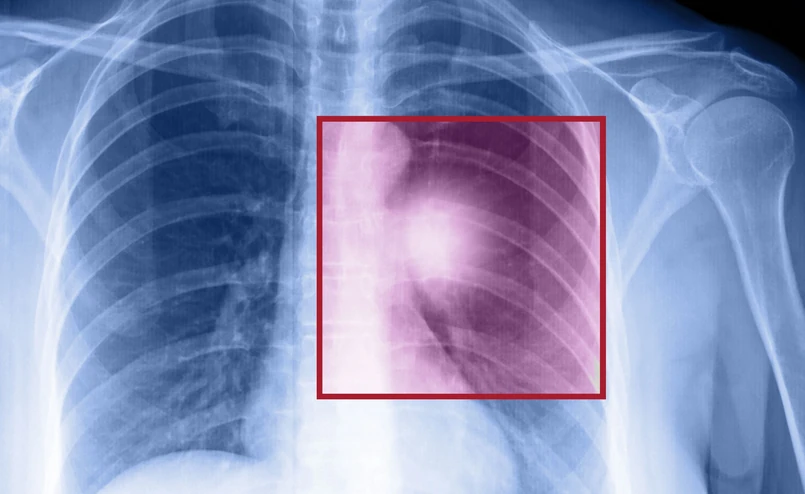

Międzynarodowe badanie FLAURA zostało przeprowadzone pod kierunkiem prof. Suresha Ramalingama z Winship Cancer Institute w Atlancie (USA) w grupie 556 pacjentów. U wszystkich zdiagnozowano lokalnie zaawansowanego lub uogólnionego (tj. z przerzutami) niedrobnokomórkowego raka płuca z obecnością mutacji w genie kodującym receptor dla naskórkowego czynnika wzrostu (EGFR). Chorzy ci nie byli wcześniej leczeni. Mniej więcej połowa z nich otrzymywała w pierwszej linii leczenia ozymertynib - drobnocząsteczkowy inhibitor kinazy tyrozynowej EGFR III generacji. Druga połowa (grupa kontrolna) była leczona jednym z dwóch starszych leków należących do inhibitorów kinazy tyrozynowej EGFR – gefitynibem bądź erlotynibem.

Onkolog zaznaczył, że zastosowanie ozymertynibu okazało się również skuteczne u pacjentów z przerzutami do mózgu, którzy mają gorsze prognozy. U pacjentów stosujących lek nowe przerzuty w ośrodkowym układzie nerwowym pojawiały się ze znacznie mniejszą częstotliwością, niż w grupie leczonej inhibitorami starszej generacji (12 proc. wobec 30 proc.). Natomiast ryzyko progresji choroby było mniejsze o 52 proc. „Znalezienie leku, który pozwala na kontrolę przerzutów do ośrodkowego układu nerwowego jest dużą sprawą” - ocenił prof. Krzakowski.